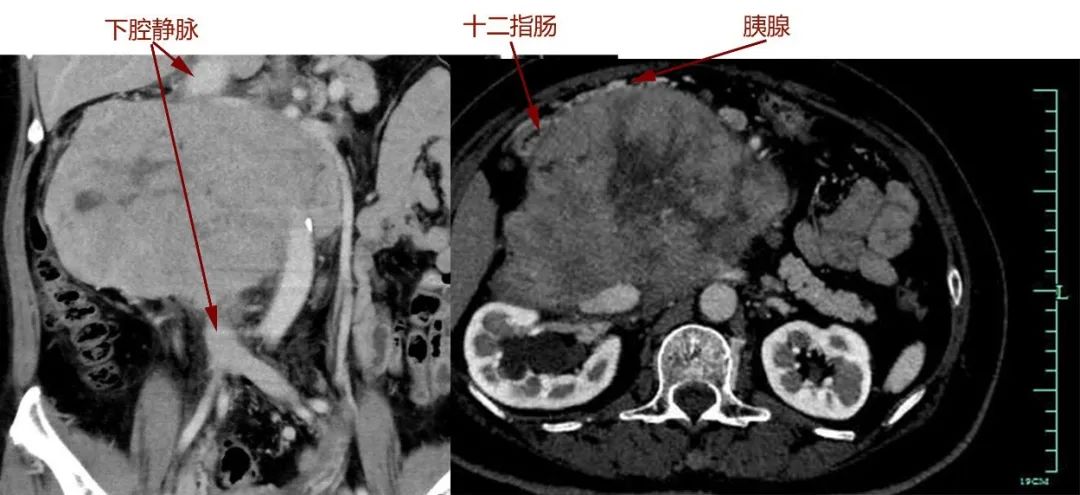

很快,吴女士转院至浙大一院肿瘤外科,完善各项术前检查后,滕教授发现情况远比最初判断严重:肿瘤与胰十二指肠、肾脏等多个脏器及主干血管关系不清,直接吞噬了腔静脉,双肾血管受累,已有轻度肾功能异常。

“我们做过很多类似的手术,但像她这样与血管黏连这么牢的很少。”滕教授表示,随即组织了放射科、泌尿外科、血管外科、肛肠外科、麻醉科、输血科等进行会诊,制定严密的手术方案。针对术中血管与脏器保留或重建的关键问题,他与肛肠外科主任、小肠移植专家吴国生教授,血管外科主任张鸿坤进行了反复探讨,“肿瘤吞噬了腔静脉,这是人体最重要的血管,就像下水管一样,稍有不慎就会大出血,造成不可挽回的后果,而肿瘤如果侵犯肠系膜,可能还要做自体小肠移植。”

手术过程和预计的一样凶险,手术团队小心翼翼将肠道、肾脏血管从肿瘤成功分离。但真正的困难很快出现:肿瘤与胰腺头部黏连,下腔静脉也被侵犯,滕教授当机立断,切断十二指肠及胰头,游离肿瘤两端下腔静脉,最后分离切除大血管部分肿瘤。由于肿瘤向血管内生长,肿瘤切下的同时血液一涌而出,早有准备的团队立即阻断下腔静脉以控制出血,快速切除肿瘤,张鸿坤主任随即缝合修补下腔静脉。万幸的是,术中发现肿瘤与肠系膜血管黏连不严重,避免了自体小肠移植。